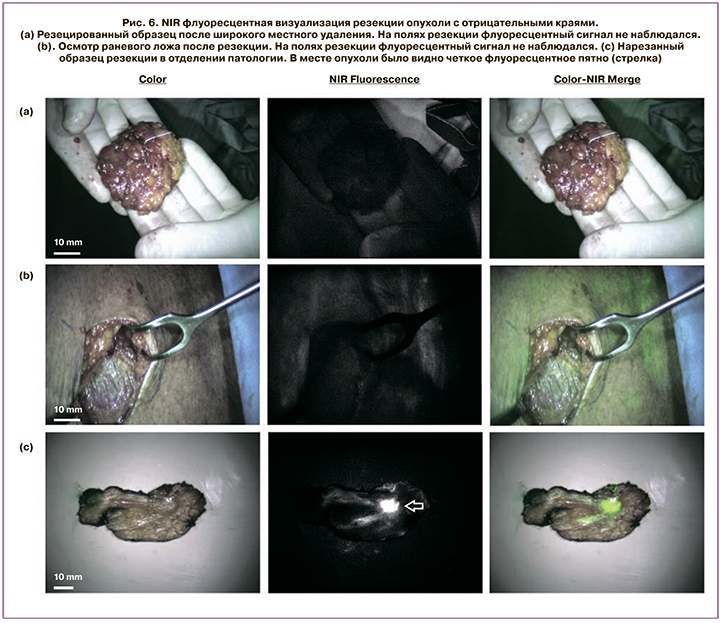

Исследование, проводимое в медицинском центре Лейденского университета, рассматривало флуоресцентную визуализацию в ближней инфракрасной области с метиленовым синим, основываясь на том факте, что метиленовый синий больше поглощается в опухолевых клетках и быстрее вымывается в доброкачественных тканях. Этот подход выявил опухоли у 20 из 24 (83%) пациентов.

На рис. 6 можно обнаружить, что флуоресцентное излучение не выявлено на поверхности резецированного образца или вдоль стенок хирургической полости, но было обнаружено после того, как образец был разрезан и опухоль была обнаружена [41].

Несомненно, данный метод показывает значительную ценность, предоставляя хороший хирургический обзор иссекаемой ткани и краев, но требует контрастного введения до или во время операции. Точность распространения контраста зависит от ткани и сосудистой проходимости в опухоли и в нормальных тканях.